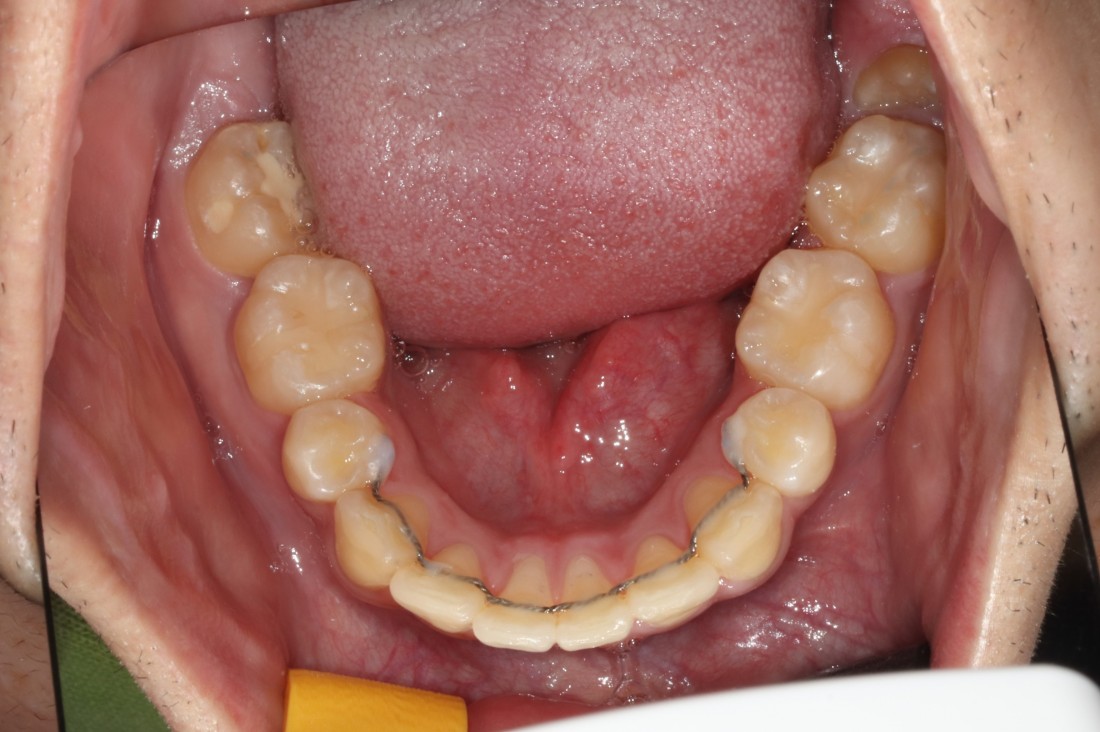

광주 개방교합 교정을 위해

방문해주신 30대 남성 환자분의

교정 전 사진입니다.

어금니를 맞닿게 하여서 입을 다물어도

윗니와 아랫니가 만나지 않는데요.